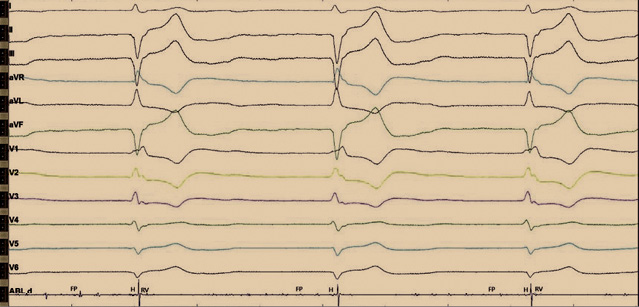

Согласно данным эхокардиографического исследования при поступлении у пациента наблюдалось расширение всех полостей сердца. Фракция выброса – 51%. Гипокинезия – сегменты 1, 7, 6, 12, 5. Отмечался склероз аорты, расширение корня и восходящего отдела. Митральная недостаточность 2-й степени – S рег. На программировании перед операцией ЭКС находился в режиме VVI(R), с базовой частотой сердечных сокращений 65 в минуту (рис. 1). Импеданс желудочкового электрода 646 Ом, чувствительность желудочкового электрода – 15,2 мВ. Порог стимуляции по желудочковому каналу 0,7 В. Срок службы составил 5 месяцев.

Рис. 1. Электрокардиограмма до операции. Постоянная желудочковая стимуляция в однокамерном режиме VVI(R) с базовой частотой 65 ударов в минуту. Длительность QRS 180 мс

Рис. 2. Интраоперационное изображение с электрофизиологического монитора во время отключения электрокардиостимулятора. Отмечается нарушение внутрижелудочкового проведения по типу блокады правой ножки пучка Гиса и блокады передней ветви левой ножки пучка Гиса. Регистрируются эндограммы c аблационного катетера: фибрилляции предсердий (FP), проводящей системы (H) и высокоамплитудные желудочковые эндограммы (RV). На данном рисунке эндограммы H и FP трудно различимы между собой, однако стимуляция с картирующего электрода данной области позволяла получить стимуляционный комплекс, идентичный с нативным. Более выраженную эндограмму пучка Гиса зафиксировать не удалось. Предположительно, это связано с ранее проведенной аблацией атриовентрикулярного соединения

Рис. 4. Электрокардиограмма после операции. Отражена постоянная желудочковая стимуляция после имплантации гисиального электрода. Стимуляционный комплекс не расширен, соответствует нативному. Определяются стимуляционный спайк, изолиния и сокращение желудочков. Имеется также второй страхующий стимул, после которого нет ответа, по типу псевдосливного комплекса. Изолиния отражает замедление проведения по специализированным клеткам проводящей системы, с последующим сокращением по системе Гиса – Пуркинье. Длительность QRS составляет 110 мс